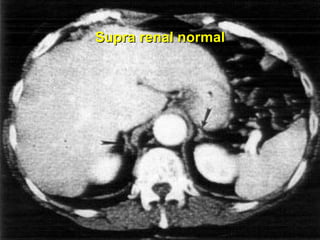

Supra renal normal

Diagnóstico Clínico / laboratorial: variável USG Imagens: TC RNM